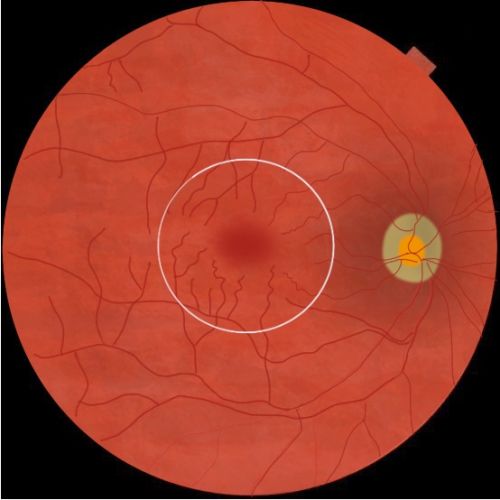

Rhegmatogenous retinal detachment (RRD) is defined as the separation of the neurosensory retina from the retinal pigment epithelium (RPE) secondary to a ‘rhegma’ or break. The macula is the central 5.5 mm circular area inside the temporal vascular arcades and contains the fovea in the central 1.5 mm which is responsible for the central vision.

Macula- or fovea-sparing (also called macula-on) retinal detachment indicates that subretinal fluid has not affected central vision and that visual acuity remains at baseline.[1]